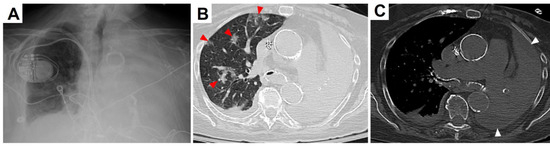

Introduction: Hypertension is occasionally associated with congenital hydronephrosis. Case report: The authors report a four-month-old boy with severe left congenital hydronephrosis and transient hypertension triggered by his first urinary tract infe...